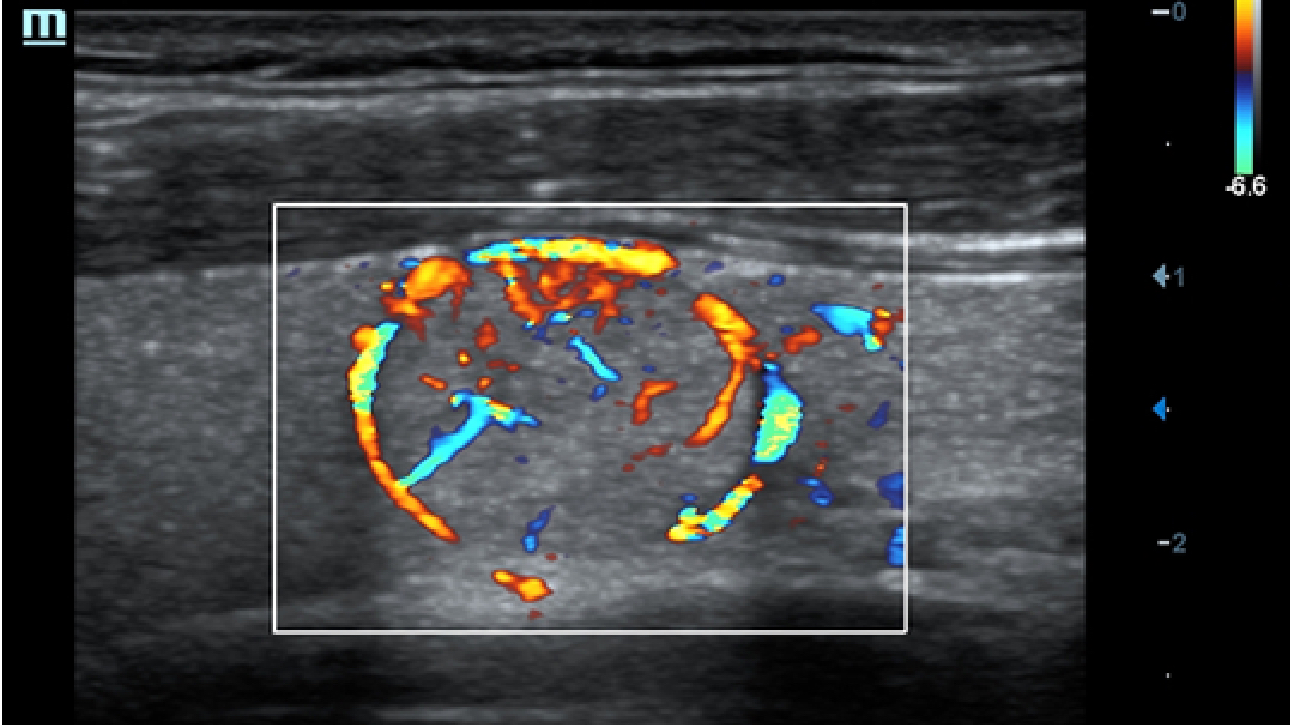

X-Insight, daha geli?mi? g?rĂŒntĂŒler elde etmek i?in kapsaml? bir ??zĂŒmdĂŒr.

Mindrayâin yeni ??zĂŒmĂŒ, geli?en en yeni ultrason teknolojileri ile birlikte, mĂŒ?terilerin g?rĂŒ?lerini klinik gerekliliklerle tam anlam?yla birle?tiren bir ??zĂŒmdĂŒr. Taptaze bir ruhla, gelece?e odaklanarak ve s?n?rs?zl???n pe?inde ko?arak, artan ?l?eklenebilirlikte sĂŒrekli olarak geli?en bir ??zĂŒmdĂŒr.

?ok y?nlĂŒ bir partner olarak, X-Insight'l? DC-60 Exp, her y?nĂŒyle gĂŒnlĂŒk klinik uygulamay? kolayl?kla ve belirsizlik olmadan y?netmenize yard?mc? olacak kapsaml? bir ??zĂŒm sunar.

MĂŒ?teri gereksinimlerine y?nelik g?rĂŒ?ler temelinde, X-Insight'l? DC-60 Exp, eXpress Clarity, eXceptional Intelligence ve eXceeding Experience ile gĂŒ?lendirilerek, hassas g?rĂŒntĂŒlemeyle yĂŒksek verimlilik sa?layacak ?ekilde tasarlanm??t?r.